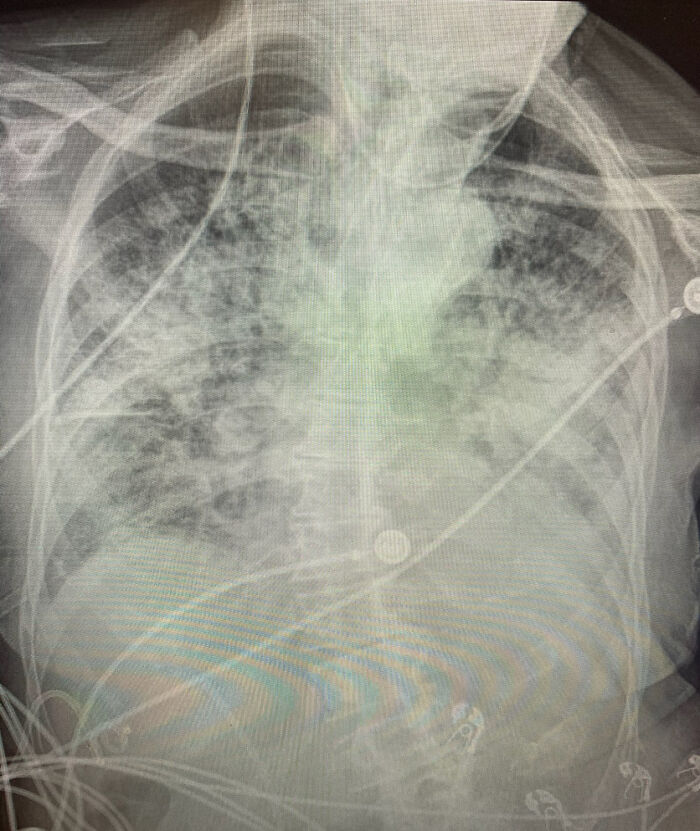

The doctor also posted photos of three lung X-rays—one of a healthy patient, one of a smoker, and one of a COVID-19 patient—to point out the differences.

The third image shows post-COVID lungs which appear to be almost fully white, meaning the lungs are severely damaged

As you can tell from the X-ray comparison, post-COVID lungs can look way worse than those of a smoker

“There are still people who say ‘I’m fine, I don’t have any issues,’ and you pull up their chest X-ray and they absolutely have a bad chest X-ray,” the doctor told CBS DFW. “You’ll either see a lot of that white, dense scarring or you’ll see it throughout the entire lung. And if you’re not feeling problems now, the fact that that’s on your chest X-ray, it sure is indicative of you possibly having problems later on.”

Apparently, even asymptomatic patients show a severe chest X-ray 70 to 80 percent of the time. Dr. Bankhead Kendall also adds that if a post-COVID patient is experiencing shortness of breath, they should stay in touch with their primary care doctor.